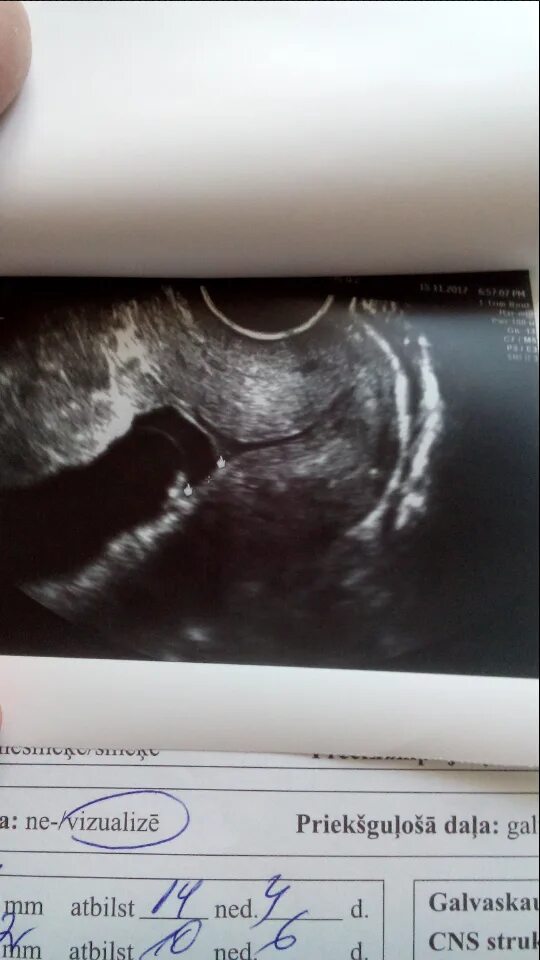

Внутренний зев воронкообразно